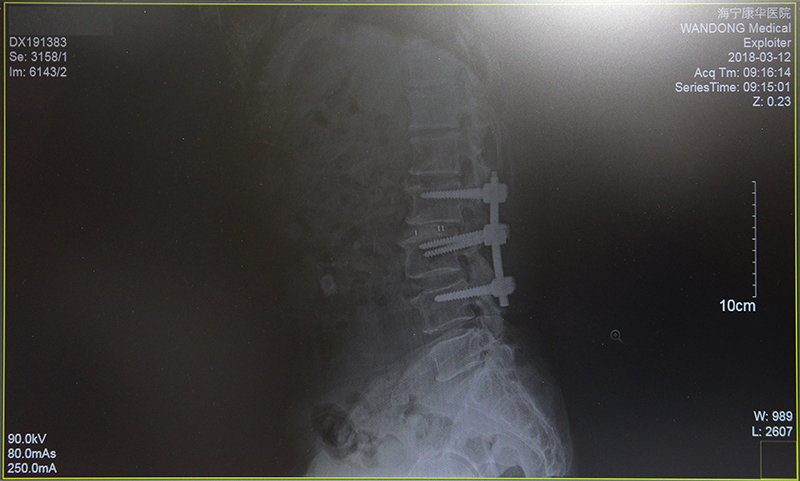

经过详细的术前检查与计划,2月2日,在鲍立峰主刀下,为沈大伯进行了“腰2/3,腰3/4减压术及腰2/3椎体融合术”。整台手术历时约3小时,较好地纠正了大伯多处突出的腰椎。第二天,沈大伯的左下肢已经恢复了肌力。随后,配合康复治疗等,两周后,大伯顺利出院了,此时的他已经基本可以靠着拐杖独立行走了。

(术后)